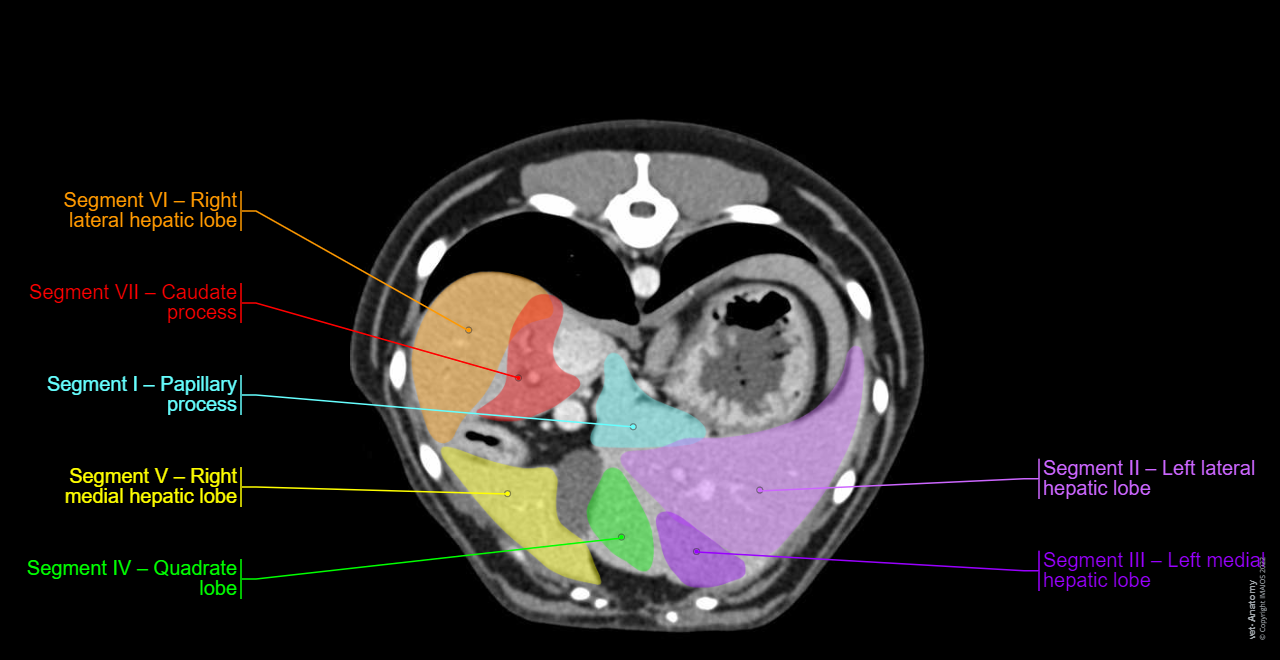

• The canine hepatic segmentation of the dog on CT is an original work from Antoine Micheau MD:

In dogs the segmentation of the liver is described with four lobes and four sublobes as well as two processes, based on anatomical consideration. This is the nomenclature used by the NAV.

For some authors, the use of a vascular anatomy of canine hepatic venous system based on the analogies between Couinaud’s segmentation of the human liver and the vascular anatomy of canine liver, could be less confounding and, therefore, more useful for the surgical (and also radiological) approach to this organ.

In vet-Anatomy, we used the publication of L. Mari and F. Acocella to provide an hepatic segmentation of the dog: the canine liver lobes and human liver segments appear comparable so we use the terminology adapted from the human Terminologia Anatomica:

SectionDivisionLobeConventional nomenclature in the NAVProposed segment numberingProposed nomenclatureEquivalent segment in human

LeftLeftLeft lateralLobus hepatis sinister lateralis

II

IIa (dorsal)

IIb (ventral)

Segment II – Left lateral hepatic lobeLeft posterior lateral segment; Segment II

Left medialLobus hepatis sinister medialisIIISegment III – Left medial hepatic lobeLeft anterior lateral segment; Segment III

CentralQuadrateLobus quadratusIVSegment IV – Quadrate lobeLeft medial segment; Segment IV

Right medialLobus hepatis dexter medialisVSegment V – Right medial hepatic lobeAnterior medial segment; Segment V

Papillary process of caudate lobeProcessus papillarisISegment I – Papillary processPosterior segment; Caudate lobe; Segment I

RightRightRight lateralLobus hepatis dexter lateralis

VI

VIa (dorsal)

VIb (ventral)

Segment VI – Right lateral hepatic lobeAnterior lateral segment; Segment VI

Caudate process of caudate lobeProcessus caudatusVIISegment VII – Caudate processPosterior lateral segment; Segment VII

No segment VIII in dogPosterior medial segment; Segment VIII

Notes for the hepatic segmentation:

• In the NAV, the caudate process and papillary process are included in a same lobe, the caudate lobe. But as these two processes differ by a right or left vascularization, they can’t be included in a same lobe in this hepatic segmentation, opposite to the human hepatic segmentation where the caudate lobe is the segment I and include the caudate process and the papillary process.

• There is no segment VIII in the dog.

Hepatic segmentation - Dog - CT